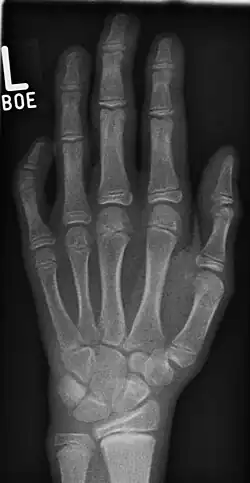

Klinodaktylia (łac. clinodactylia) – mała wada wrodzona (cecha dysmorficzna) polegająca na bocznym lub przyśrodkowym skrzywieniu palca dłoni bądź stopy w płaszczyźnie dłoni lub stopy. Najczęściej dotyczy piątego, małego palca, który jest wtedy zgięty w stronę dośrodkową. Klinodaktylia spowodowana jest hipoplazją kości środkowego paliczka. Niewielką klinodaktylię można wykryć, obserwując przebieg linii zgięciowych palców, które w klinodaktylii przebiegają skośnie, a nie równolegle. Wystąpienie klinodaktylii może się wiązać z różnymi zespołami genetycznymi, m.in. zespołem Silvera-Russella[1], zespołem Feingolda i zespołem Downa.